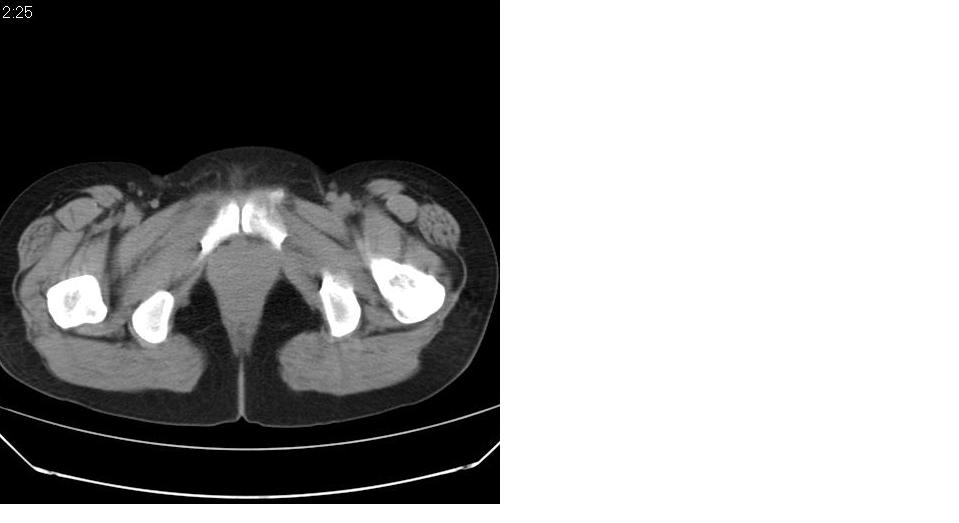

女 35岁,下腹部坠感疼,其它病史不详。图象顺序有点乱。

定位于盆腔附件,有囊性密度,有脂肪密度、还有骨密度;应该是比较典型的卵巢畸胎瘤。